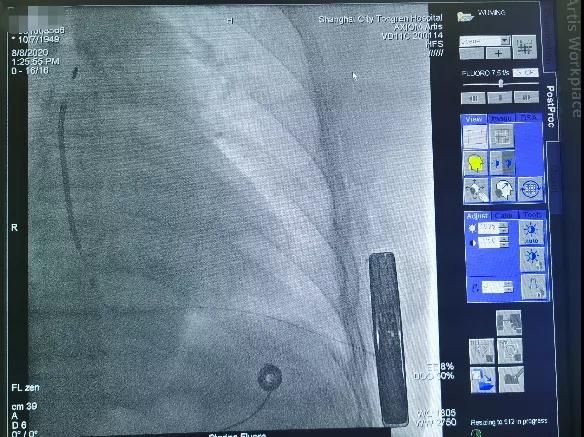

于剑突下切开皮肤2cm,逐层分离皮下组织至筋膜层,通过隧道穿引针连接囊袋,再沿胸骨向上约14cm处切开皮肤1cm,逐层分离皮下组织至筋膜层,通过隧道穿引针连接剑突下切口,使用隧道穿引针将45cm长的3501除颤电极从囊袋经隧道送至剑突下切口,固定电极中段,再使用隧道穿引针将电极经隧道送至胸骨上方切口,固定头端。连接脉冲发生器A209,置入囊袋内,逐层缝合筋膜层及皮下组织,进行DFT测试,采用50HZ,200MA交流电方式进行诱颤,SICD正确识别,经首次65J除颤成功,除颤阻抗58欧姆。缝合皮肤 ,术区纱布覆盖,包扎,弹力绷带加压包扎止血。手术圆满成功,耗时约1小时。